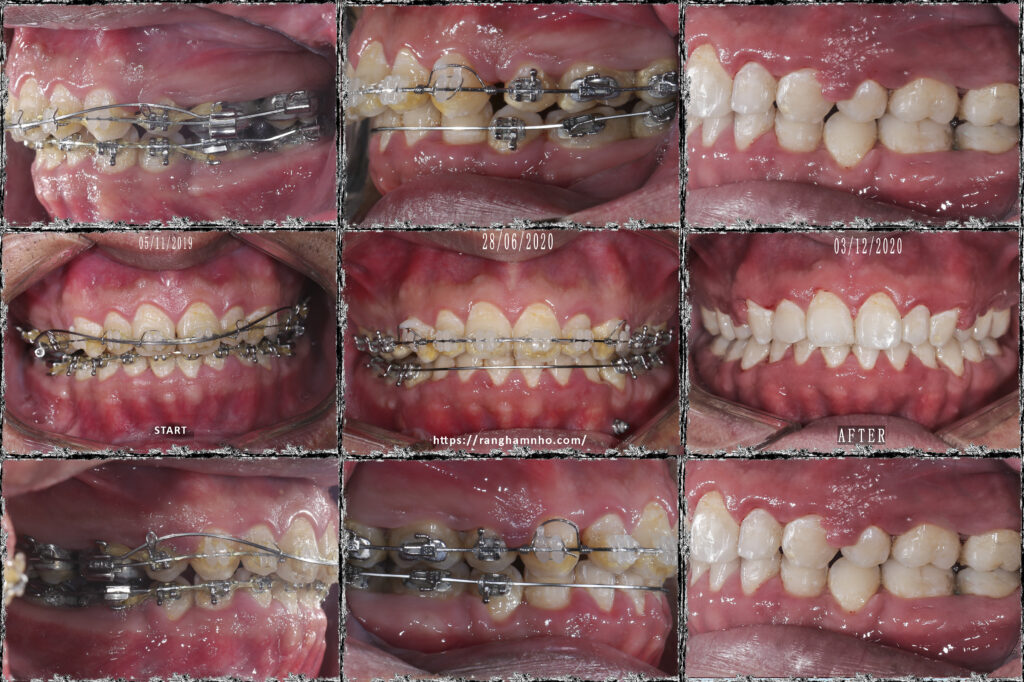

Điều trị những trường hợp bật chân răng do niềng hỏng là rất khó khăn và phức tạp. Trường hợp này là một bệnh nhân được niềng răng ở nước ngoài, sau đó hết thời gian lao động mà bệnh nhân chưa hoàn thành điều trị và được chuyển về việt nam để điều trị tiếp. Tuy nhiên, khi BN đến với phòng khám làm gặp tình trạng mất torque rất nặng ở hàm dưới đến mức trên CBCT không còn cả bản xương ngoài- trong. Nên nhóm răng cửa hàm dưới không thể can thiệp gì hơn.

Kế hoạch: chỉnh torque, đóng nốt khoảng và chỉnh khớp cắn 2 hàm, hoàn thiện và kết thúc trong 1 năm

Kết quả cười hở lợi cải thiện rõ rệt. Điều trị cười hở lợi bằng chỉnh nha khá hiệu quả trong trường hợp này